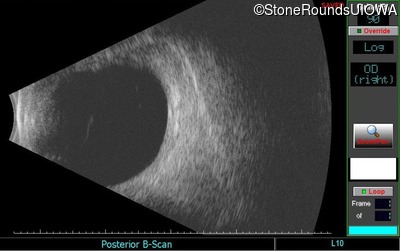

B-Scan Ultrasonography - Right - 20/32 +2 sc

Exemplar